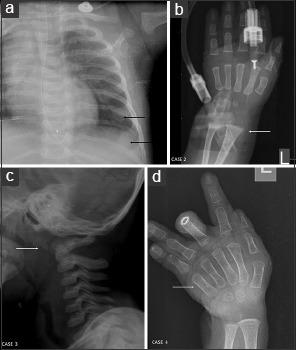

Menkes disease (MD) is an X-linked recessive neurodegenerative disorder caused by mutations in gene. Depending on the residual activity, manifestation may be classical MD, occipital horn syndrome, or distal motor neuropathy. Neurological sparing is expected in female carriers. However, on rare occasions, females may manifest with classical clinical phenotype due to skewed X-chromosome inactivation, X-autosome translocation, and XO genotype. Here, we describe a small series of probands with MD and their response to copper histidine therapy. This series also includes a female with X-13 translocation manifesting neurological symptoms.

All the four children in our series had developmental delay, recurrent respiratory tract infections, hair and skeletal changes, axial hypotonia, tortuous vessels on imaging, low serum copper, ceruloplasmin, and elevated lactate. Fetal hypokinesia and fetal growth retardation were present in two cases. Failure to thrive was present in three children and only one child had epilepsy. Subcutaneous copper histidine was administered to all children. The average time lapse in the initiation of treatment was 20.3 months, and average duration of follow-up was 14.3 months.

门克斯病(MD)是一种由基因 突变引起的X连锁隐性神经退行性疾病。根据残余 活性,临床表现可能为典型的MD、枕角综合征或远端运动神经病。预计女性携带者不会出现神经系统症状。然而,在极少数情况下,女性可能由于X染色体失活偏斜、X-常染色体易位和XO基因型而表现出典型的临床表型。在此,我们描述了一小系列MD先证者及其对组氨酸铜治疗的反应。该系列还包括一名表现出神经系统症状的X-13易位女性。

我们系列中的所有4例患儿均有发育迟缓、反复呼吸道感染、毛发和骨骼改变、轴性肌张力低下、影像学上血管迂曲、血清铜、铜蓝蛋白降低以及乳酸升高。2例患儿有胎儿运动减少和胎儿生长受限。3例患儿有生长发育不良,只有1例患儿有癫痫。所有患儿均接受了皮下注射组氨酸铜治疗。开始治疗的平均时间间隔为20.3个月,平均随访时间为14.3个月。